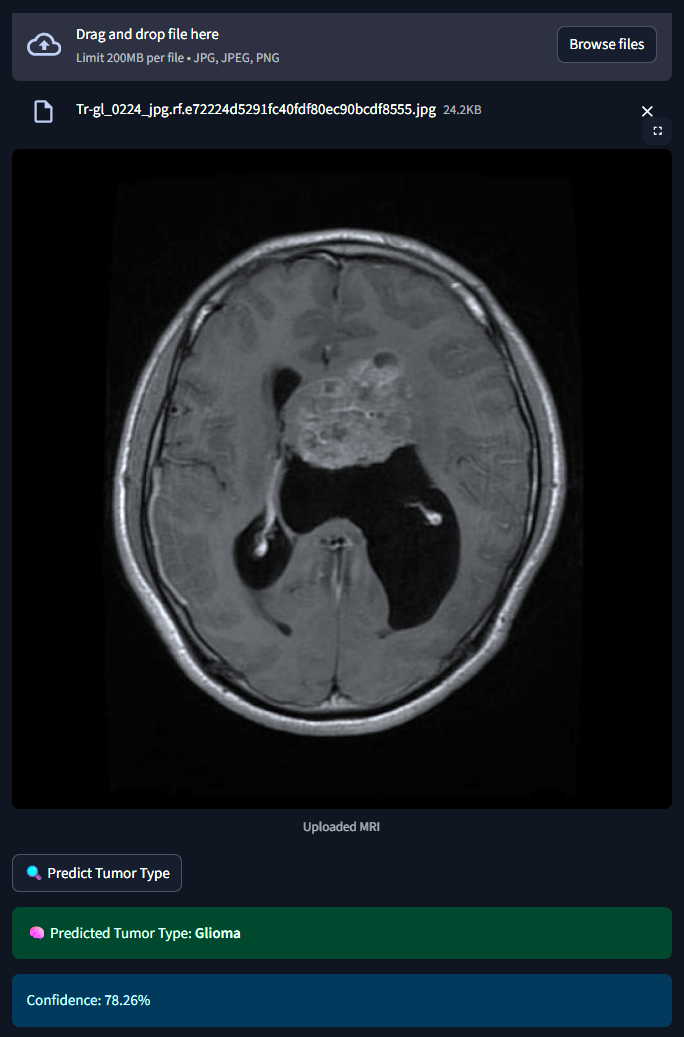

The system classifies MRI brain scans into one of four categories - Glioma, Meningioma, Pituitary Tumor or No Tumor. It uses both a Custom Convolutional Neural Network (CNN) and MobileNetV2 Transfer Learning for classification. An interactive Streamlit web app allows users to upload MRI images and receive real-time tumor predictions with probability scores.

1) Dataset :- 2,443 MRI images labeled and categorized by medical experts. 2) Preprocessing :- Used ImageDataGenerator for rescaling, rotation, zoom and flipping to augment limited data. 3) Model 1 (Custom CNN) :- Built from scratch with 3 convolutional layers, dropout and softmax classification. 4) Model 2 (MobileNetV2) :- Fine-tuned transfer learning model using pretrained ImageNet weights. 5) Training :- Used callbacks like EarlyStopping and ModelCheckpoint to optimize training and avoid overfitting. 6) Evaluation :- Tracked model performance using confusion matrix, accuracy/loss plots, and classification reports. 7) Deployment :- Developed a Streamlit web app for real-time image classification and visualization.

1) Preventing Overfitting on a relatively small medical dataset. 2) Class Imbalance, requiring strategic augmentation. 3) Maintaining Inference Speed for a smooth web experience. 4) Memory and file handling limitations in deploying large models via Streamlit.